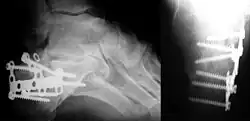

Die medizinische Diagnostik ist bis heute das wichtigste Anwendungsgebiet der Röntgenstrahlen. Die Strahlenbelastung konnte im Laufe der Zeit immer weiter gesenkt werden, gleichzeitig wurden die Aufnahmen immer detailreicher. Durch Verwendung mathematischer Verfahren lassen sich heute mit neuen bildgebenden Verfahren wie der Computertomographie dreidimensionale Abbildungen des Körperinneren erstellen.